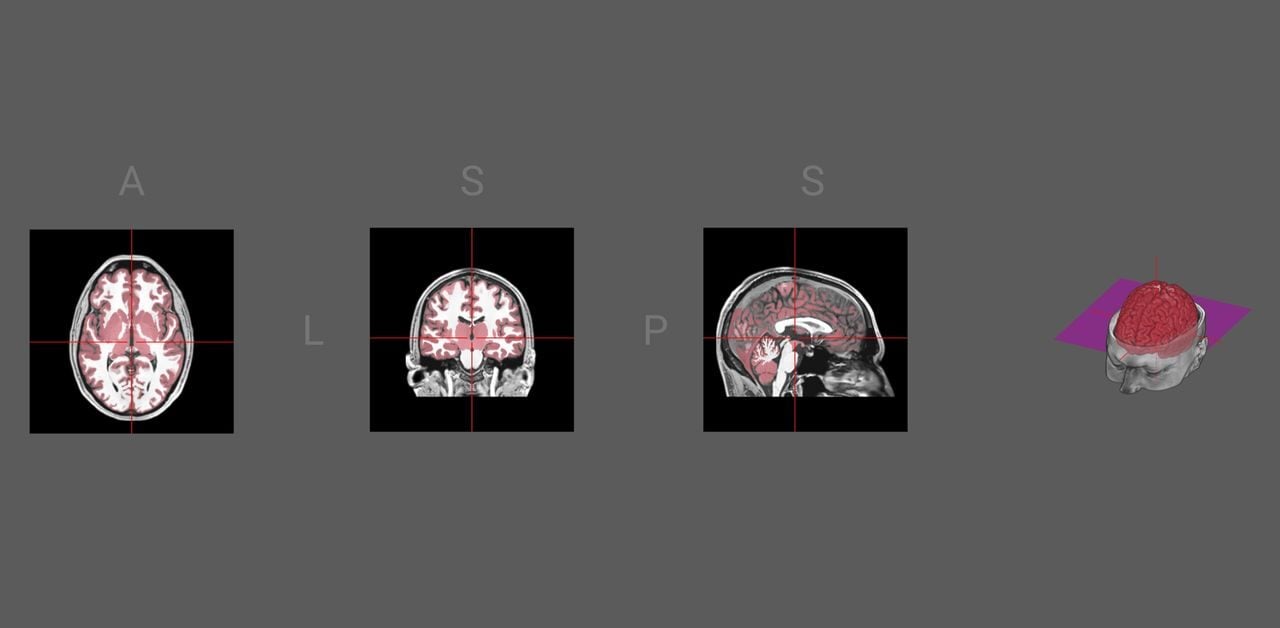

Want to 3D print your brain? You can!

dicom